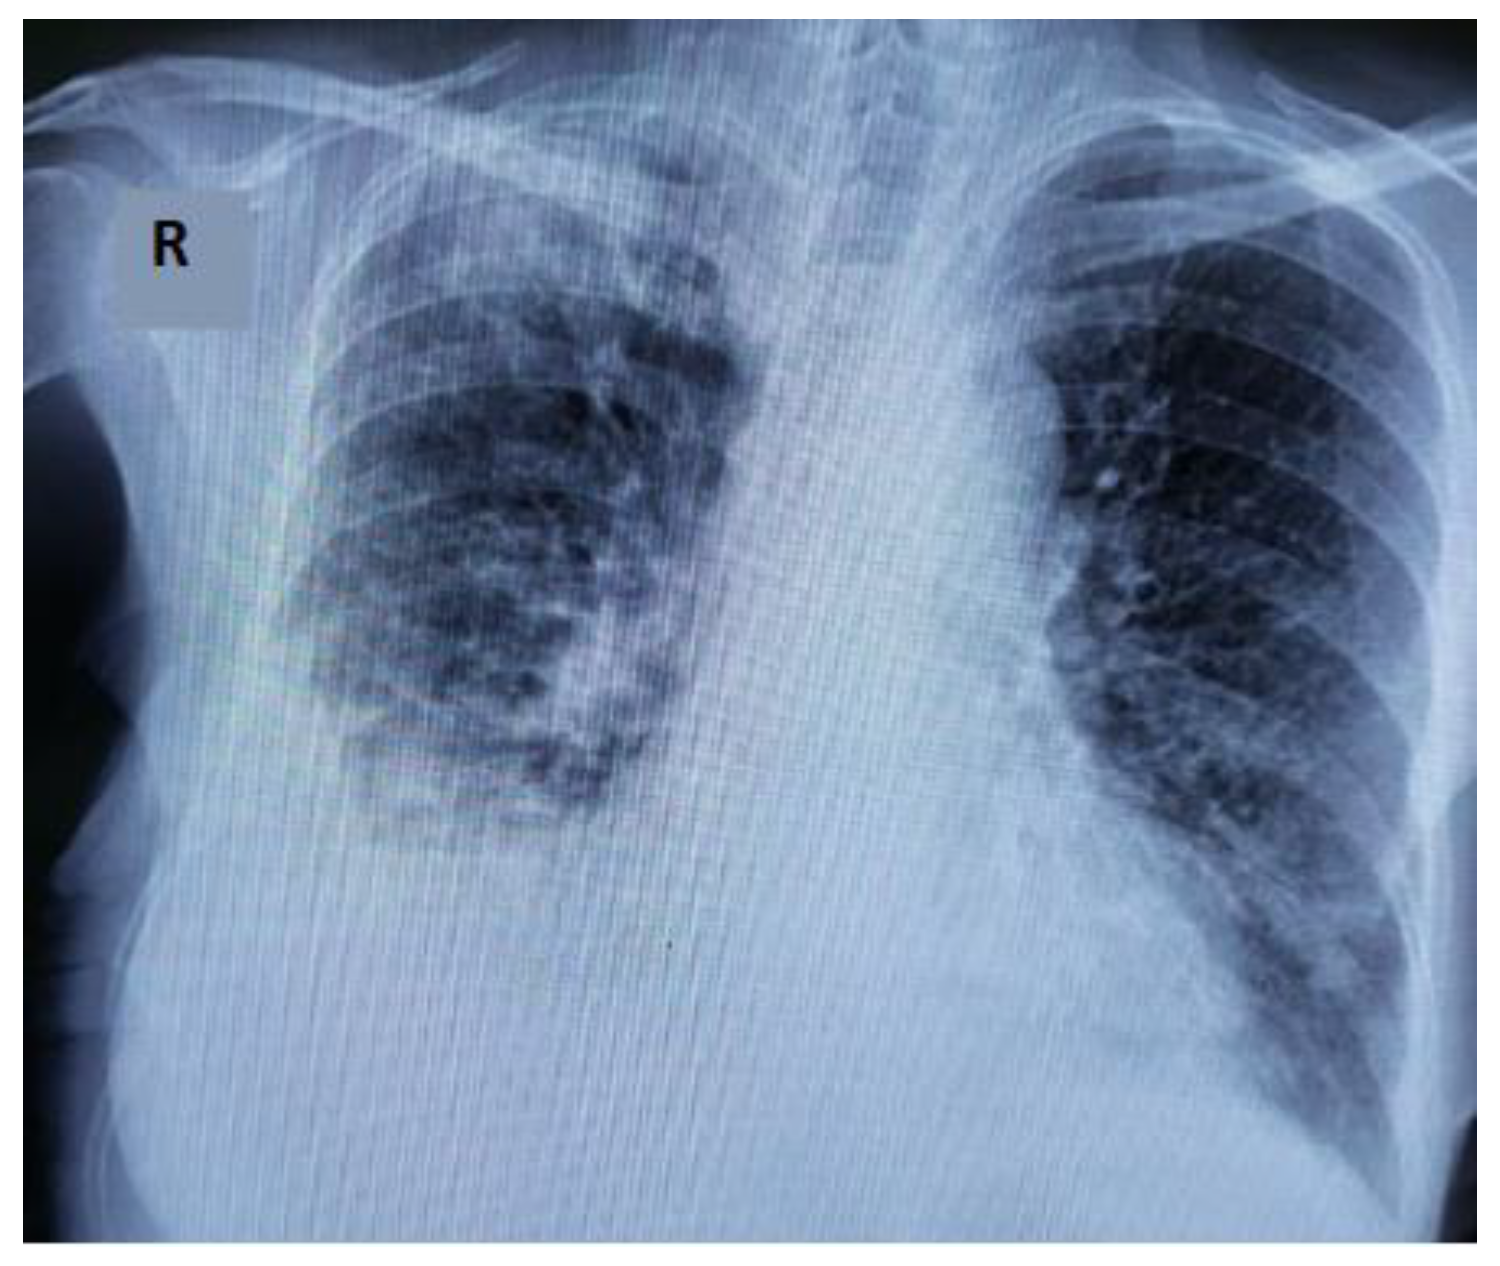

- Egashira, R. High-Resolution CT Findings of Myositis-Related Interstitial Lung Disease. Medicina 2021, 57, 692. [Google Scholar] [CrossRef]

- Rorat, M.; Jurek, T.; Simon, K.; Guziński, M. The chest radiographic scoring system in initial diagnosis of COVID-19: Is a radiologist needed? Adv. Clin. Exp. Med. 2021, 30, 797–803. [Google Scholar] [CrossRef]